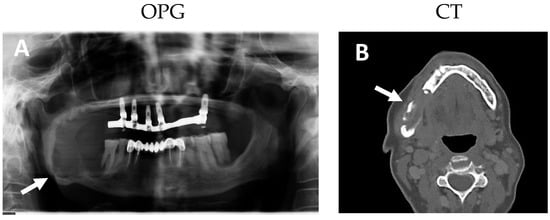

2. Results

2.1. Clinical and Histological Manifestations of the Tumors

4.2. Magnetic Resonance Imaging